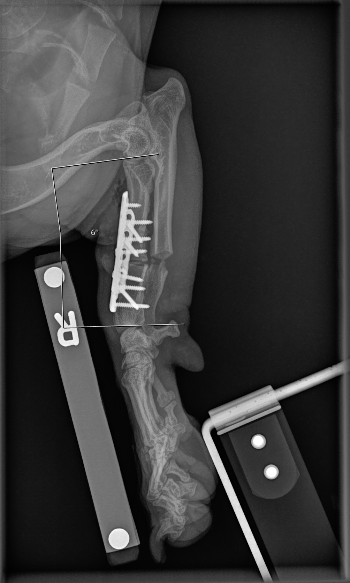

UPDATE CONTROLE ORTHOPEED

Geweldig, nog geweldiger, geweldigst nieuws! 🙌🏼

Mijn poot is GOEDGEKEURD! ✔️

Ik heb nog een lichte standafwijking van 4 graden, maar die komt overeen met mijn andere poot en is volledig normaal en acceptabel voor een teckel. 🐾

De vergroeiing van mijn belangrijkste bot ontwikkelt zich goed en zal na verloop van tijd volledig genezen.

Het bot groeit zelfs alweer terug in de ruimte tussen de gedraaide botten! Dit overtreft alle verwachtingen.